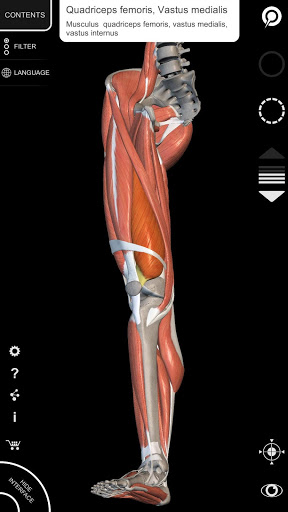

"Anatomy 3D Atlas" дозволяє легко та інтерактивно вивчати анатомію людини.

Завдяки простому та інтуїтивно зрозумілому інтерфейсу можна спостерігати кожну анатомічну структуру під будь-яким кутом.

Анатомічні 3D-моделі особливо деталізовані та мають текстури з роздільною здатністю до 4k.

АНАТОМІЧНІ 3D МОДЕЛІ

• Кістково-м’язова система

• Обертайте та збільшуйте кожну модель Тривимірний простір

• Візуалізація м’язів через рівні шарів від поверхневих донизу до найглибших

• Вибравши модель або шпильку, з’явиться відповідний анатомічний термін

• Опис м’язів: походження, приєднання, іннервація та дія